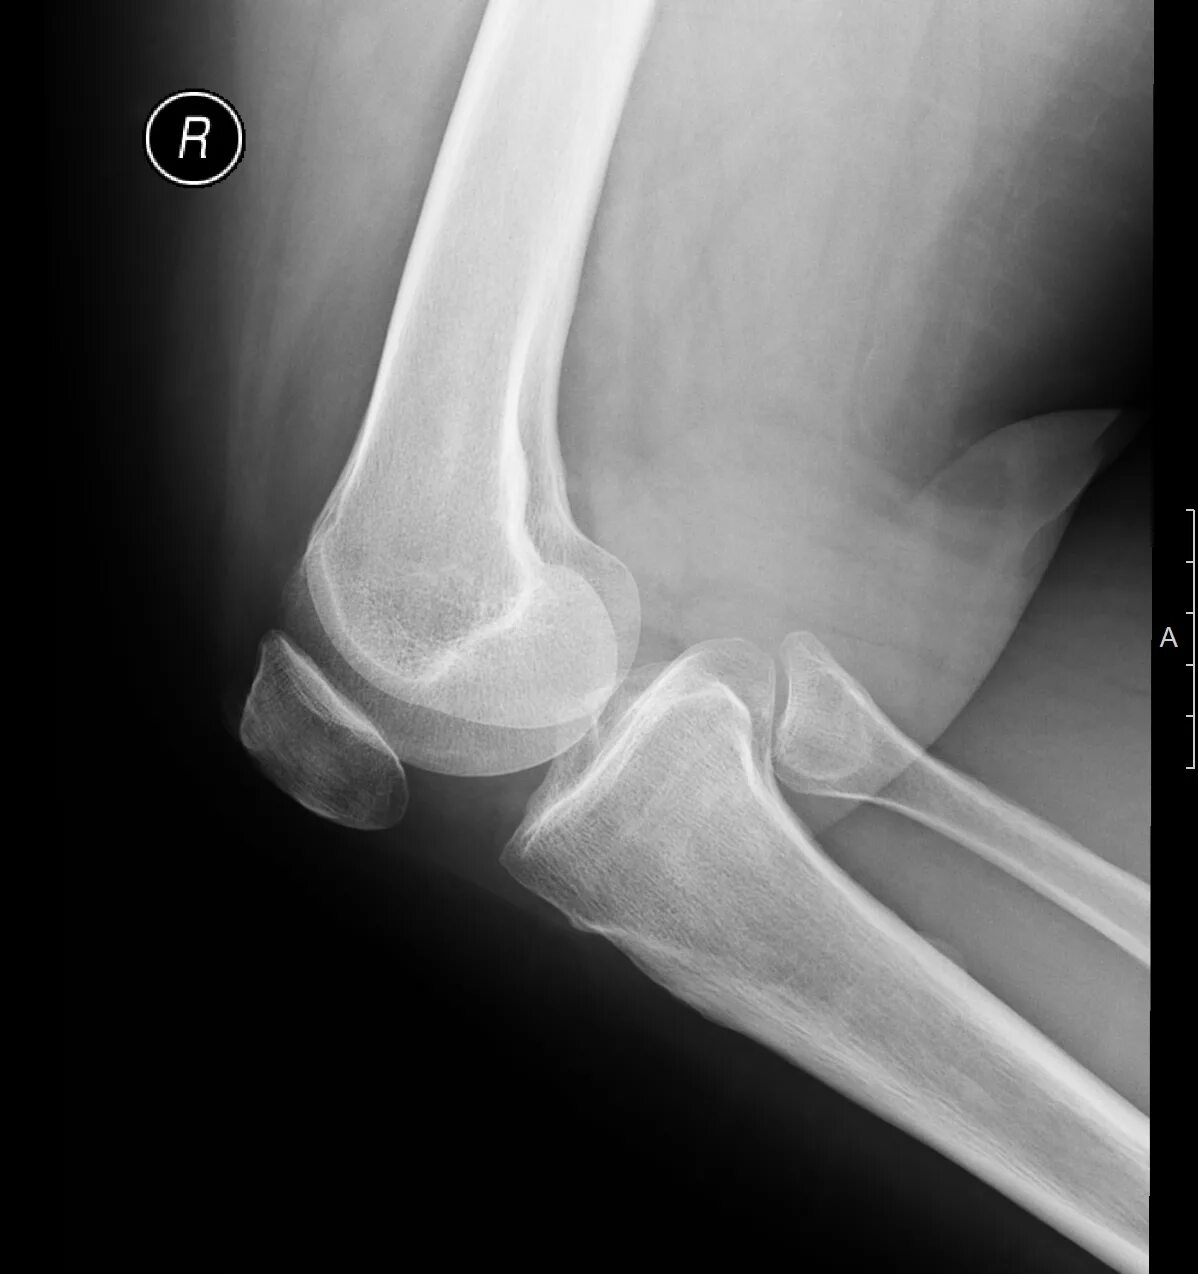

Обызвествление сухожилий мышц